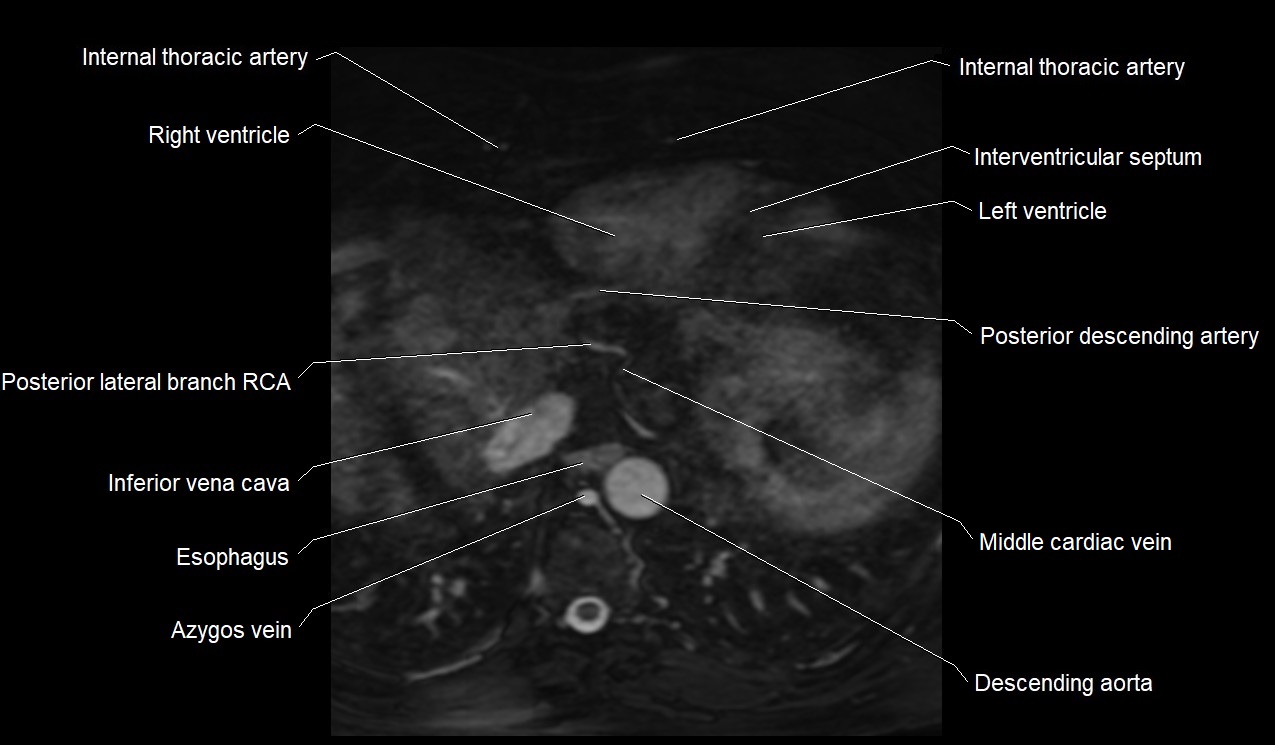

MRI image